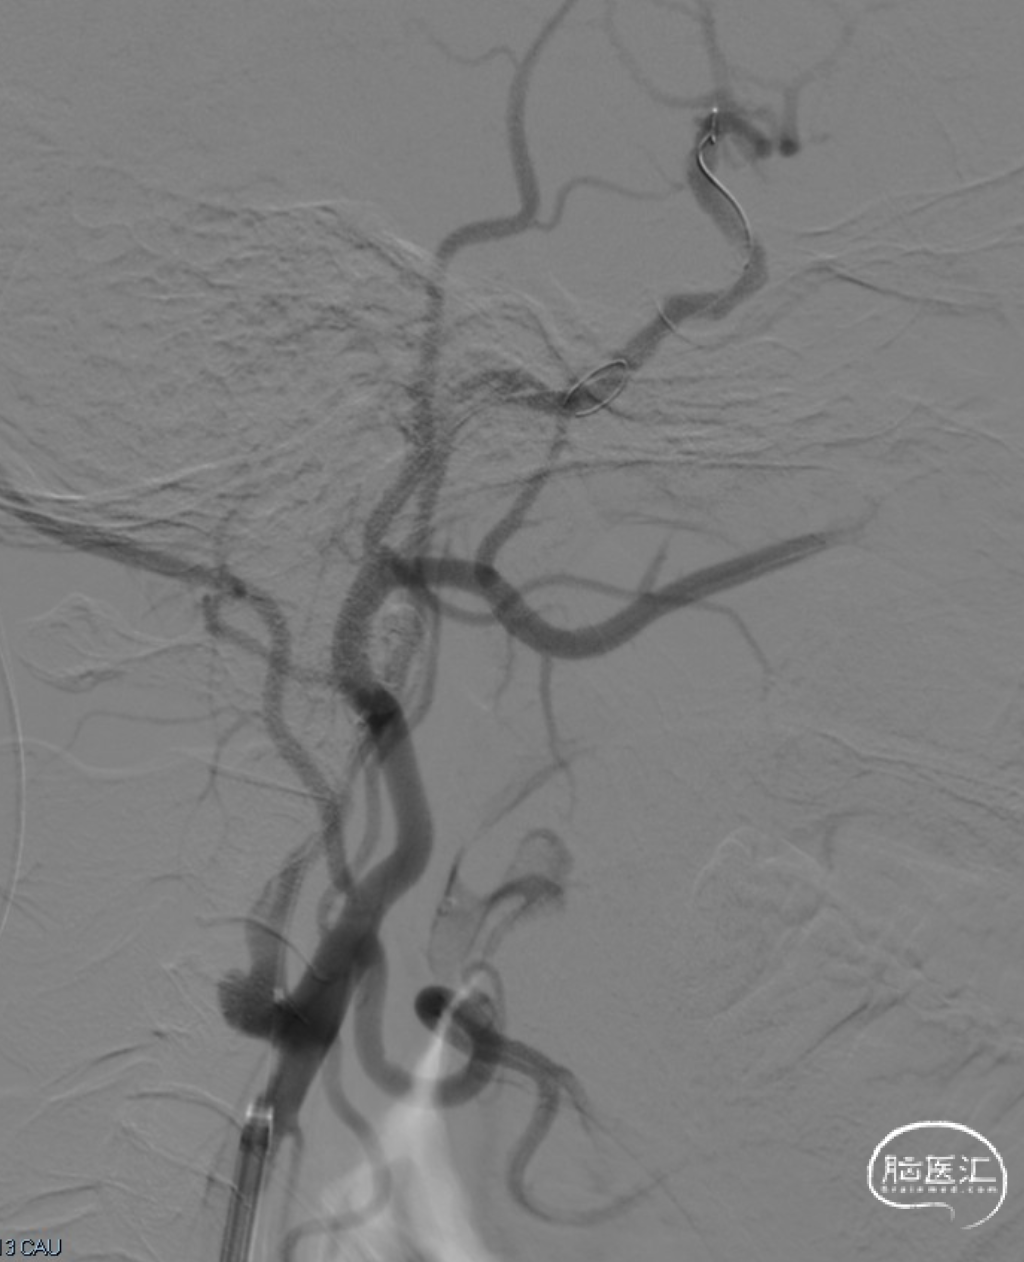

术前DSA造影显示左侧颈内动脉自起始段闭塞,C6眼段以上供血区由颈外动脉眼动脉反向代偿供血,左侧大脑中动脉供血区由前交通动脉代偿供血。

造影后引导下,以0.014in×185cm 微导丝小心通过右侧颈内动脉C1段闭塞处至C3段。随后以0.014in×300cm 微导丝在SL-10微导管支撑下通过闭塞段,成功进入大脑中动脉M1段。

沿微导管送入4.0×30mm Syphonet®取栓支架,于M1-C7段释放作为栓塞保护装置。

沿4.0×30mm Syphonet®取栓支架输送导丝送入3.0×12mm SacSpeed®球囊扩张导管,自C1-C7段分次扩张,每次释压后跟进中间导管至C5段,复查造影显示血流通畅。

造影提示C5-C6段仍有残余狭窄。于是利用SacSpeed®球囊扩张导管收回部分Syphonet®取栓支架,在狭窄处直接扩张。

撤回SacSpeed®球囊扩张导管,复查造影。